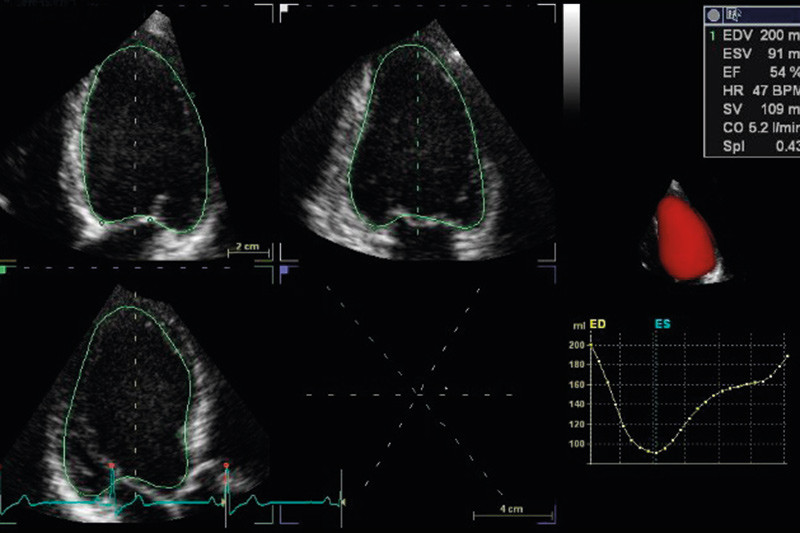

Automatisk volumanalyse med angivelse av venstre ventrikkels ejeksjonsfraksjon (EF) kan gjøres fra tre ortogonale plan (4) eller fra hele fullvolumet, med fremstilling av volumkurve i hele hjertesyklusen (fig 1). 3D-ekko har en teoretisk fordel ved at volumet ikke beregnes ut fra en geometrisk modell, men kan estimeres direkte fra fullvolumopptak. Man unngår også å gjennomskjære apeks slik at volumet blir falskt lavt, noe som ofte er tilfellet ved konvensjonell todimensjonal avbildning. Metoden er validert mot MR-undersøkelse av hjertet, med god overenstemmelse for venstre ventrikkels volumer og ejeksjonsfraksjon (2, 4) – (7).